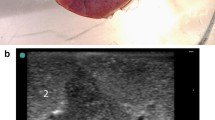

Observation of gross specimens

When observing lung tissue visually, the injection site was seen to contain black magnetic fluid without diffusion after injection. A small amount of bleeding with no hematoma was observed. The magnetic fluid solidified in the lung to form a mass of gel. Its shape and position did not change with external force when the injection site was touched with the tip of the forefinger (Fig. 6).

A pursuit magnet was used to provide an applied magnetic field that could attract the magnetic gel, and this drew the lung tissue together to protrude from the lung surface (Fig. 7). No tearing or wound was observed in the lung tissue and no magnetic gel escaped after removal of the pursuit magnet.

Observation of gross specimens

On days 1, 3, 5, and 7 after the operation, the rabbits were euthanized and the chest was opened. A pursuit magnet was used to provide an applied magnetic field to the lung surface to observe the localization effect. We observed that the magnetic gel was attracted by the applied magnetic field, and that the local area was involved. The lung tissue where the hypothetical SPN located was protruded from the surface of the lung (Fig. 10).